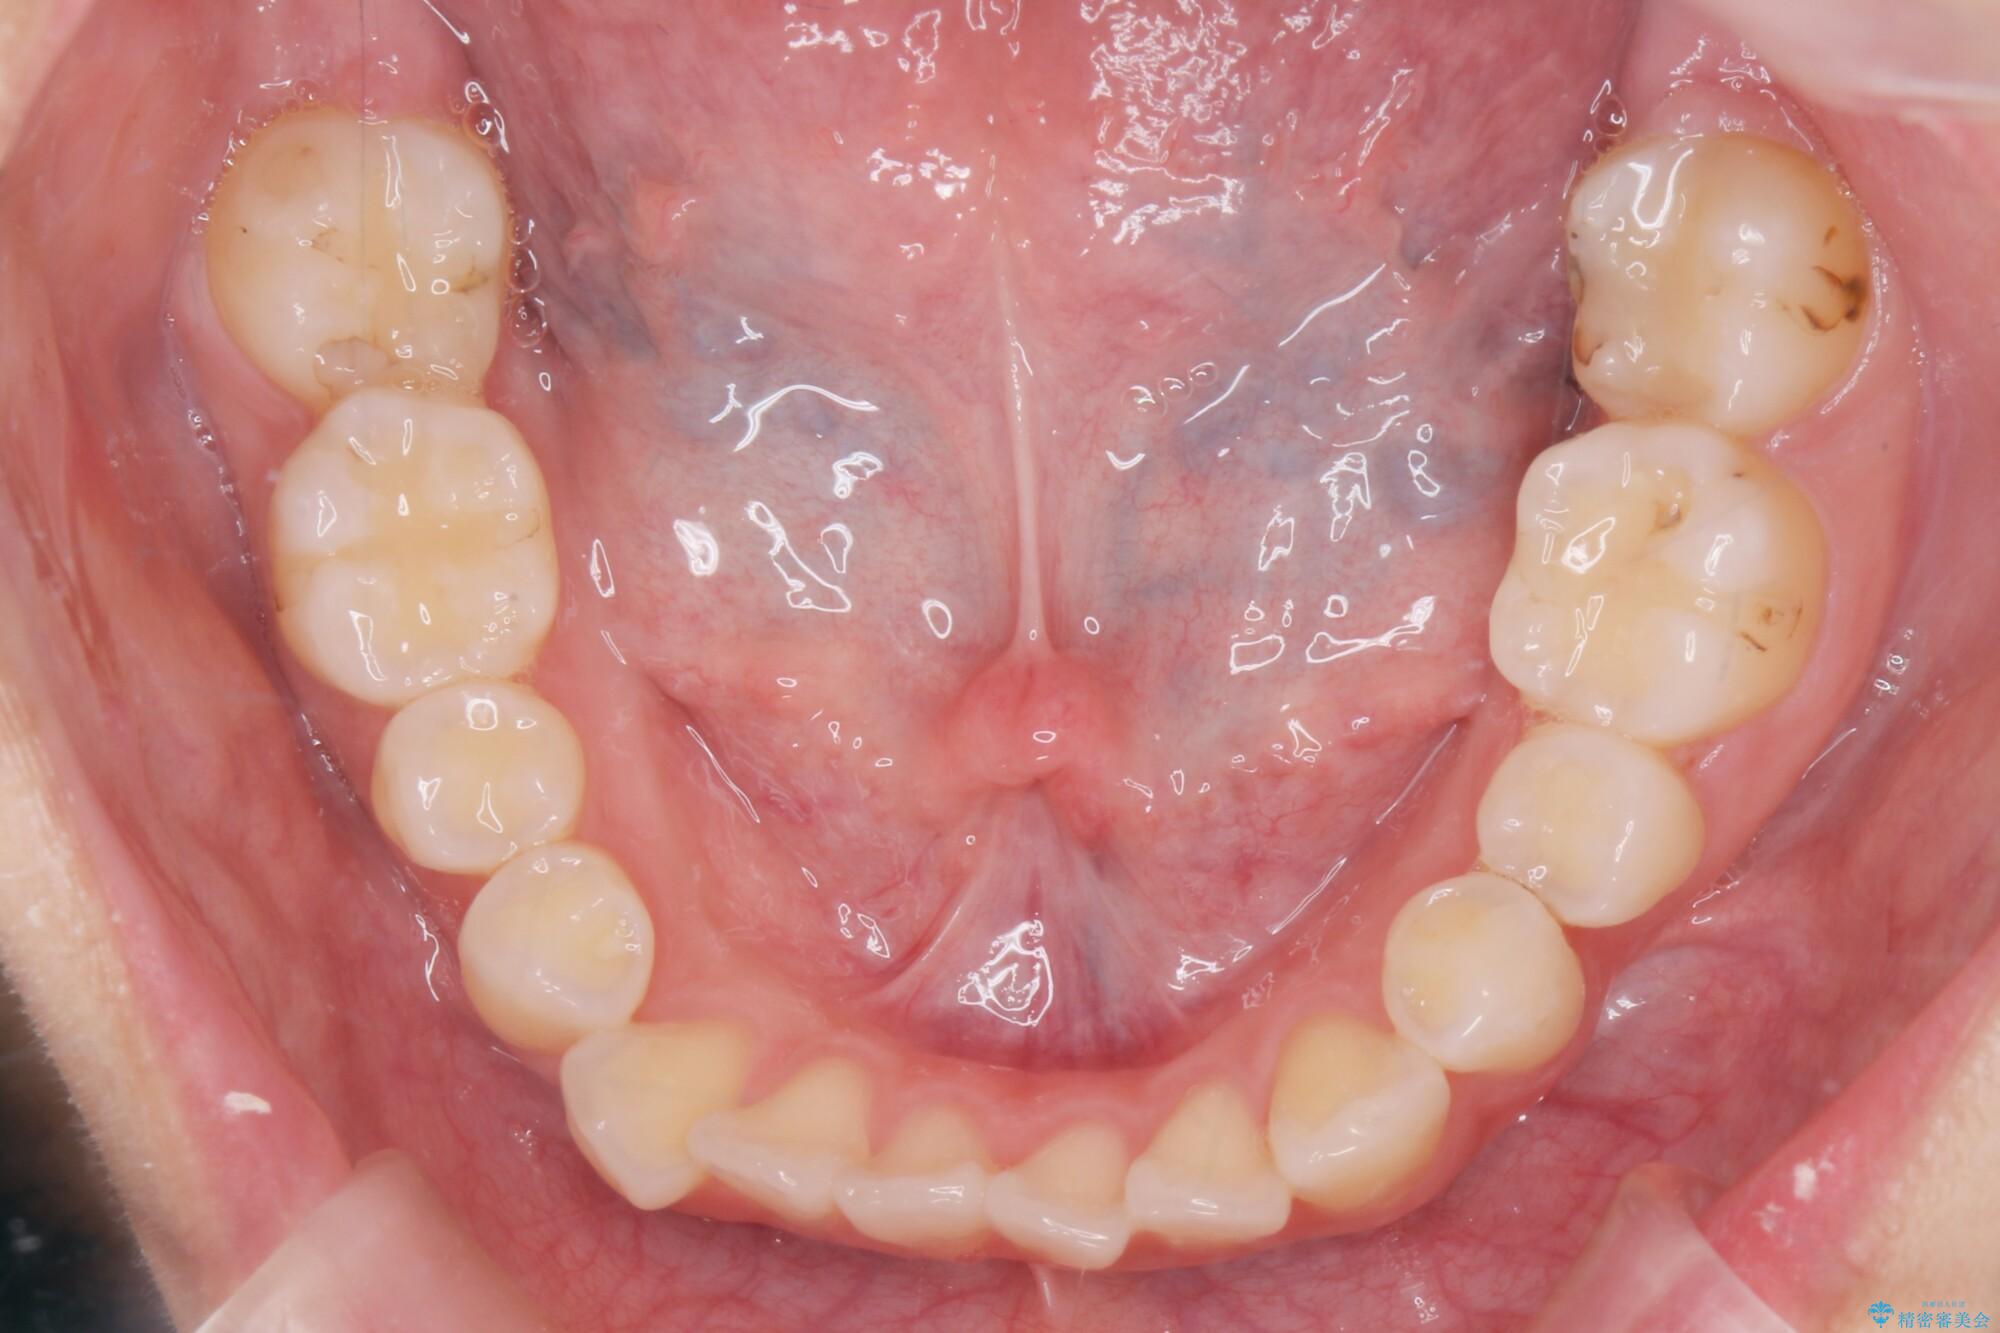

噛まない前歯と捻じれてしまった歯を改善したいと、矯正治療を希望された患者様です。

マルチブラケットを用いた非抜歯のワイヤー矯正で噛み合わせと歯並びを改善していきます。

1年で歯並び、嚙み合わせともにしっかりと改善されました。